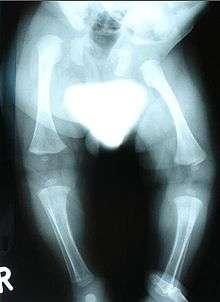

- X-ray, to look for bone abnormalities

Congenital distal spinal muscular atrophy (congenital dSMA) is a hereditary genetic condition characterized by muscle wasting (atrophy), particularly of distal muscles in legs and hands, and by early-onset contractures (permanent shortening of a muscle or joint) of the hip, knee, and ankle. Affected individuals often have shorter lower limbs relative to the trunk and upper limbs. The condition is a result of a loss of anterior horn cells localized to lumbar and cervical regions of the spinal cord early in infancy, which in turn is caused by a mutation of the TRPV4 gene. The disorder is inherited in an autosomal dominant manner.[1] Arm muscle and function, as well as cardiac and respiratory functions are typically well preserved.[2]

- Arthrogryposis